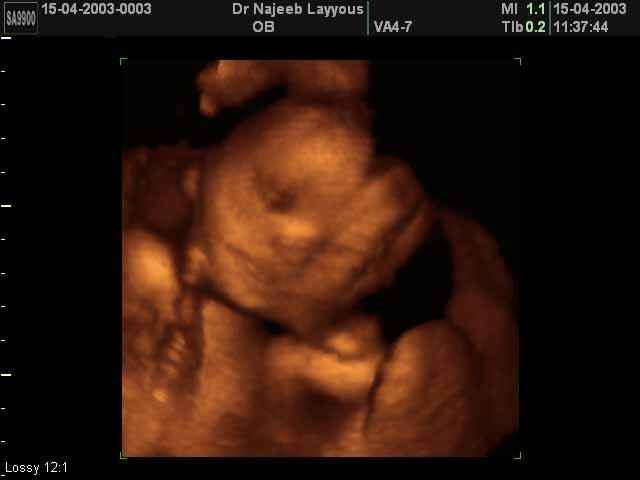

- 3D Fetal Profile Ultrasound Scan Photos

3D Second Trimester Ultrasound Scan Photos-second part of pregnancy | Dr N Layyous